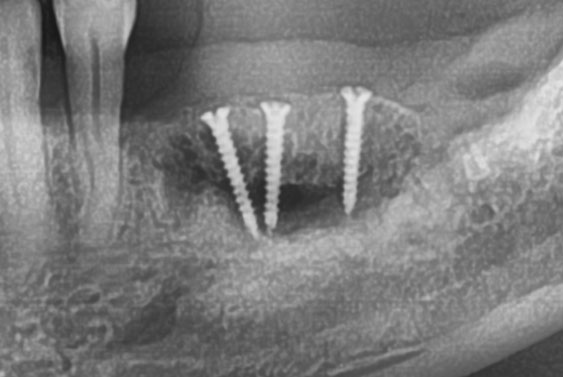

임플란트 할 때 잇몸뼈이식이 중요한 이유?

많은 분들이 임플란트를 하면서 잇몸뼈이식도 하게 됩니다.

잇몸뼈이식을 하는 이유는 식립하는

임플란트를 잘 잡아주는 힘

이 필요하기 때문 인데요.

한번 하면 최대한 오래 사용하고자 하는 임플란트, 시작할 때 잇몸뼈이식을 잘 해야 하겠죠!